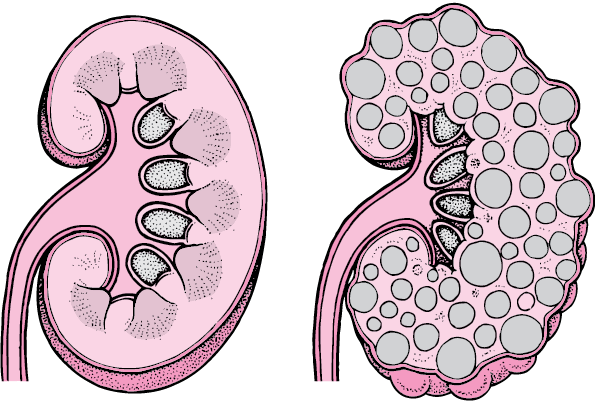

Trong y học, echo thận hay còn gọi là siêu âm thận, là một kỹ thuật chẩn đoán hình ảnh không xâm lấn, sử dụng sóng siêu âm tần số lớn để xây dựng những hình ảnh chân thật về cấu trúc, kích thước, dấu hiệu điển hình của các bệnh lý về thận. Đặc biệt, siêu âm thận có giá trị cao trong việc phát hiện các bệnh lý khu trú ở thận như sỏi thận, nang thận, áp xe thận hay thận ứ nước.

Bệnh lý thận lan toả có thể gặp ở cả hai quả thận với những đặc điểm như: